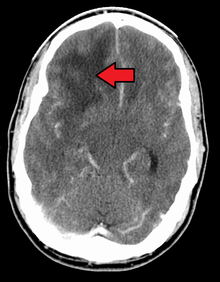

The tumor may take on a variety of appearances, depending on the amount of hemorrhage, necrosis, or its age. A CT scan will usually show an inhomogeneous mass with a hypodense center and a variable ring of enhancement surrounded by edema. Mass effect from the tumor and edema may compress the ventricles and cause hydrocephalus.

When viewed with MRI, glioblastomas often appear as ring-enhancing lesions. The appearance is not specific, however, as other lesions such as abscess, metastasis, tumefactive multiple sclerosis, and other entities may have a similar appearance.[43] Definitive diagnosis of a suspected GBM on CT or MRI requires a stereotactic biopsy or a craniotomy with tumor resection and pathologic confirmation. Because the tumor grade is based upon the most malignant portion of the tumor, biopsy or subtotal tumor resection can result in undergrading of the lesion. Imaging of tumor blood flow using perfusion MRI and measuring tumor metabolite concentration with MR spectroscopy may add value to standard MRI in select cases by showing increased relative cerebral blood volume and increased choline peak respectively, but pathology remains the gold standard for diagnosis and molecular characterization.